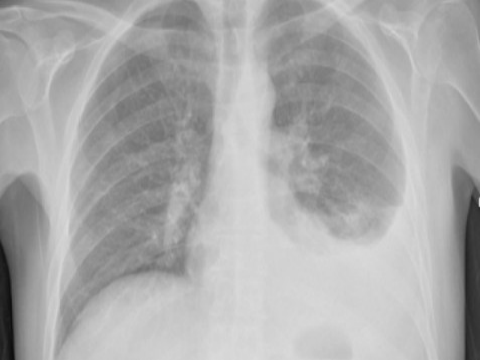

Xu hướng giảm mắc và tử vong do lao ở Việt Nam và trên thế giới